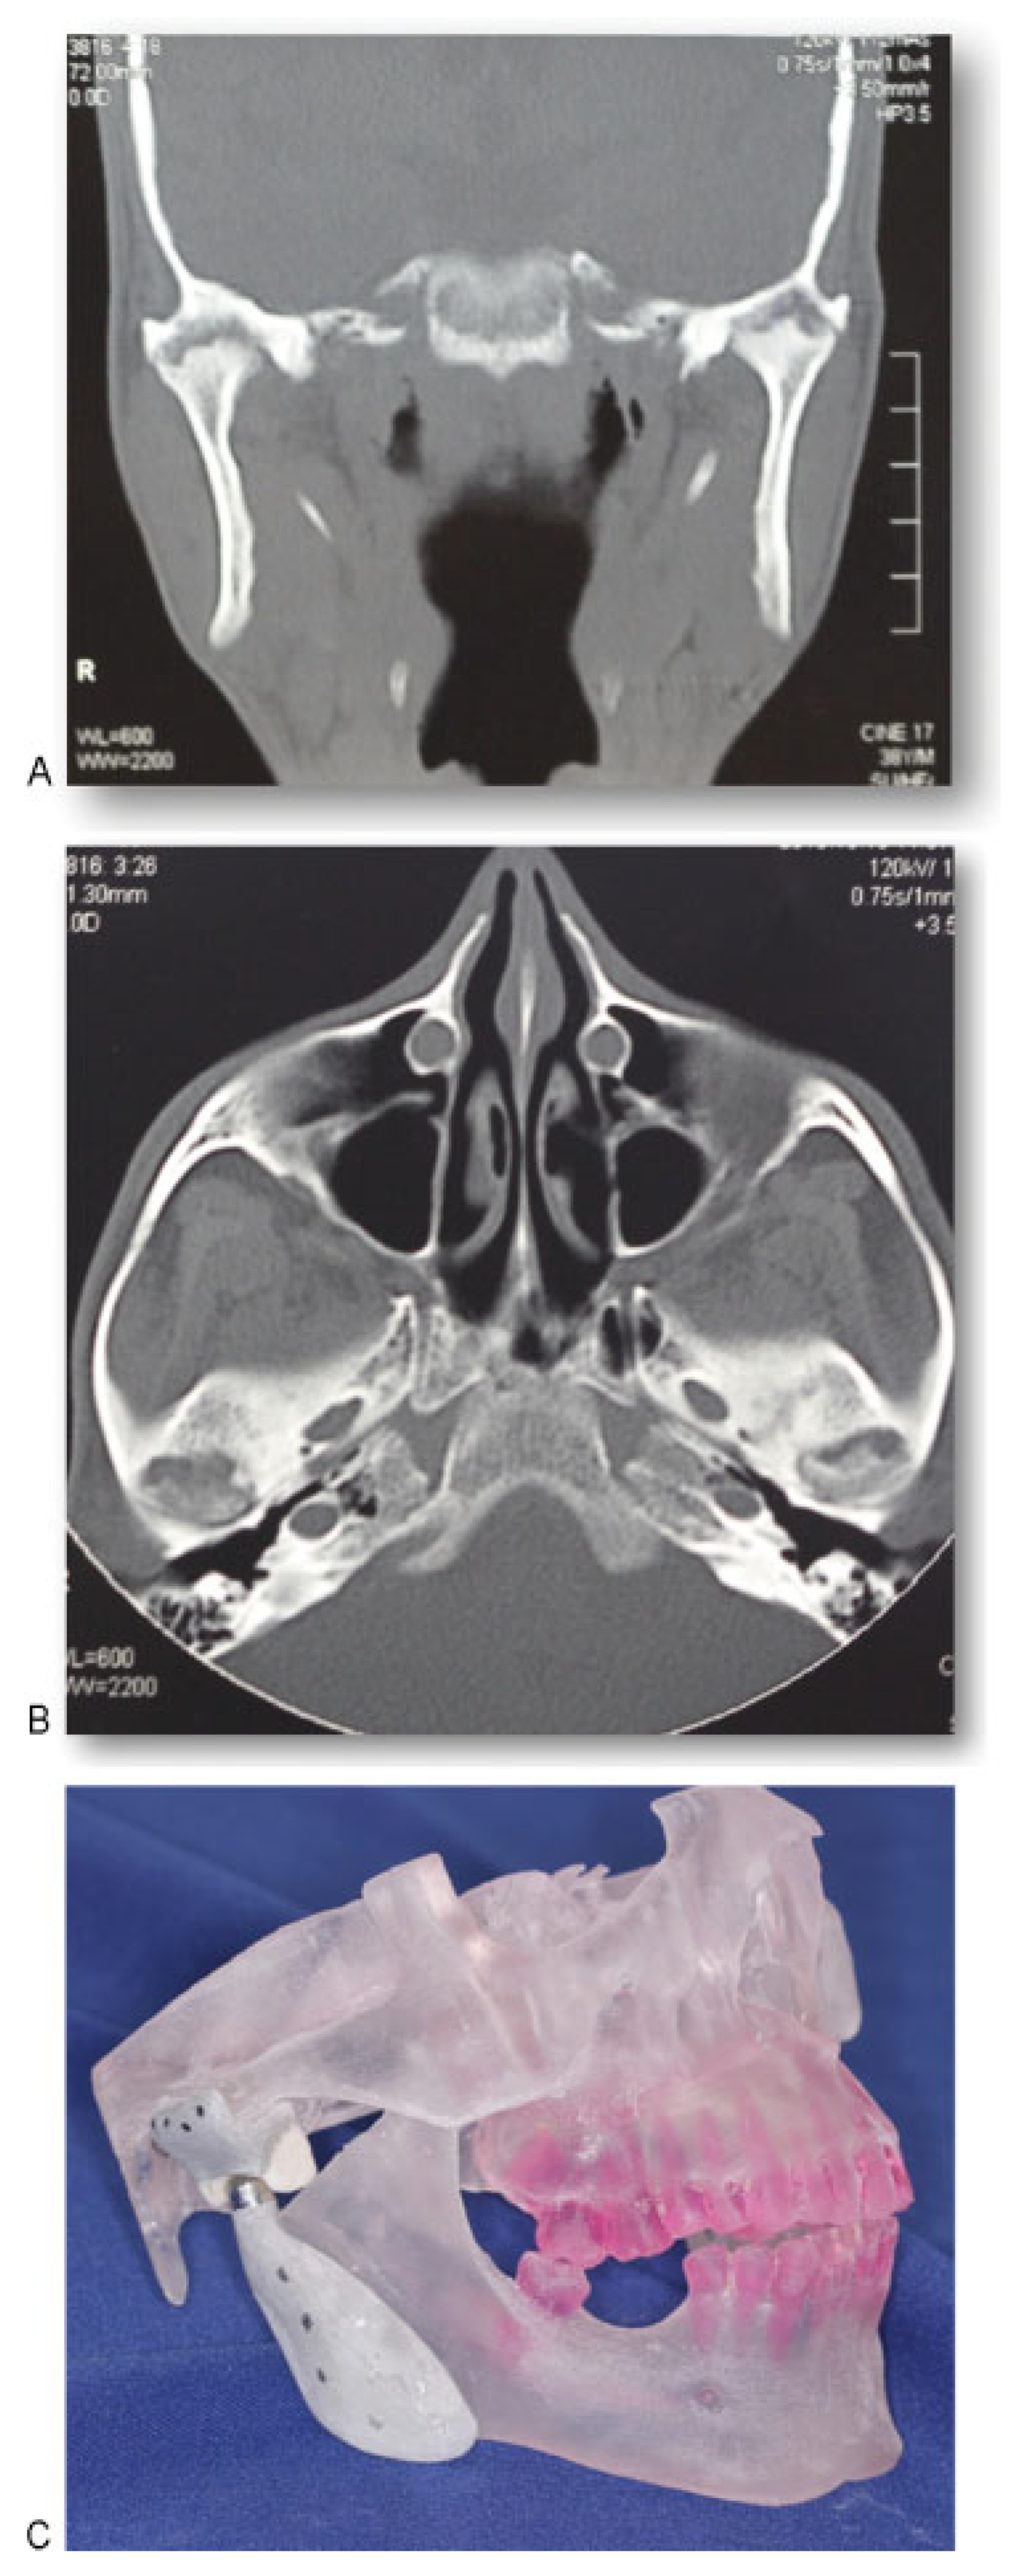

A 38-year-old man with AS was referred to the division of Oral and Maxillofacial Surgery of Piracicaba Dental School for limitation of mouth opening 16 months ago. Examination revealed that he had a 9 mm interincisal opening (Figure 1), with no lateral or protrusive mandibular movements, including severe rigidity of the cervical, thoracic, and lumbar spine. The patient reported that he underwent surgery on both shoulders in 2006 due to the joint involvement caused by the disease. In 2008, the AS affected the right iliac-femoral joint, and the patient had a femoral prosthesis inserted. The same occurred the following year with the left iliac-femoral joint. Computed tomography (CT) of both TMJs confirmed severe ankylosis (Figure 2A,B). Because of the extent of his disease, resection of the ankylotic mass and replacement of both TMJs by total alloplastic joint was indicated [9]. A stereolithographic prototype was built from the CT sections and a mock surgery was done on the prototype for fabrication of individualized prostheses (Figure 2C). The mandibular component is made of titanium, with the condylar head of cobalt–chromium–molybdenum alloy. The fossa component is designed to replace the articulating surface of the TMJ comprised by the glenoid fossa and the articular eminence. It is made of ultra-high molecular weight polyethylene. Its spherical radius allows excellent articulation to the spherical head of the mandibular component. We decided to use a customized prosthesis because it is easier to adapt at the mandibular ramus, eliminating adjustments; the occlusion is better achieved; the length of the surgery is smaller and, consequently, the morbidity and postoperative pain are reduced. Because of the rigidity of his cervical spine and limitation of mouth opening, the induction of general anesthesia was performed by fiberoptic nasoendoscopy. During the surgery, a bodily tilt of the operating table by 20 degrees on each side was required due to the rigidity of his cervical spine. Surgical access was through bilateral preauricular and submandibular incisions. Via the preauricular approach, the affected condyle was removed, the glenoid fossa was smoothed, and the articular component of the prostheses was inserted (Figure 3A,B). From the submandibular incision, the coronoid process was removed and the condylar implant inserted. The same operative sequence was done on the opposite side (Figure 4A,B). Postoperative CT confirmed correct placement of the total joint prostheses (Figure 5A,B). Wooden spatulas and a Therabite (Atos Medical, West Allis, WI) appliance were used for postoperative physiotherapy, and interincisal distance has been maintained at 20 mm at 1-year follow-up (Figure 6).

Figure 2. (A) Axial view of computed tomography (CT) showing ankylosis of temporomandibular joints (TMJs). (B) Coronal view of CT showing ankylosis of TMJs. (C) Stereolithographic prototype was built from the CT sections.